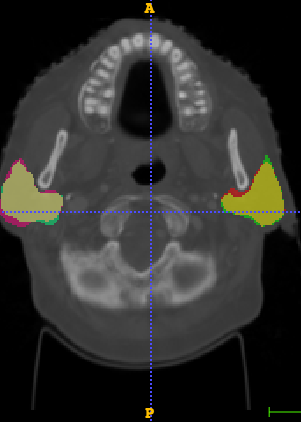

In Chapter 6, we propose an end-to-end, atlas-free 3D convolutional deep learning framework for fast and fully automated whole-volume HaN anatomy segmentation [115]. Our deep learning model, called AnatomyNet, segments OARs from head and neck CT images in an end-to-end fashion, receiving whole-volume HaN CT images as input and generating masks of all OARs of interest in one shot. AnatomyNet is built upon the popular 3D U-net architecture, but extends it in three important ways: 1) a new encoding scheme to allow auto-segmentation on whole-volume CT images instead of local patches or subsets of slices, 2) incorporating 3D squeeze-and-excitation residual blocks in encoding layers for better feature representation, and 3) a new loss function combining Dice scores and focal loss to facilitate the training of the neural model. These features are designed to address two main challenges in deep-learning-based HaN segmentation: a) segmenting small anatomies (i.e., optic chiasm and optic nerves) occupying only a few slices, and b) training with inconsistent data annotations with missing ground truth for some anatomical structures. We collect 261 HaN CT images to train AnatomyNet, and use MICCAI Head and Neck Auto Segmentation Challenge 2015 as a benchmark dataset to evaluate the performance of AnatomyNet. The objective is to segment nine anatomies: brain stem, chiasm, mandible, optic nerve left, optic nerve right, parotid gland left, parotid gland right, submandibular gland left, and submandibular gland right. Compared to previous state-of-the-art results from the MICCAI 2015 competition, AnatomyNet increases Dice similarity coefficient by 3.3% on average. AnatomyNet takes about 0.12 seconds to fully segment a head and neck CT image of dimension , significantly faster than previous methods. In addition, the model is able to process whole-volume CT images and delineate all OARs in one pass, requiring little pre- or post-processing. We demonstrate that our proposed model can improve segmentation accuracy and simplify the auto-segmentation pipeline. These contributions are released as an open-source software package called AnatomyNet, which is publicly available555https://github.com/wentaozhu/AnatomyNet-for-anatomical-segmentation. Portions of this chapter were published as part of [115].